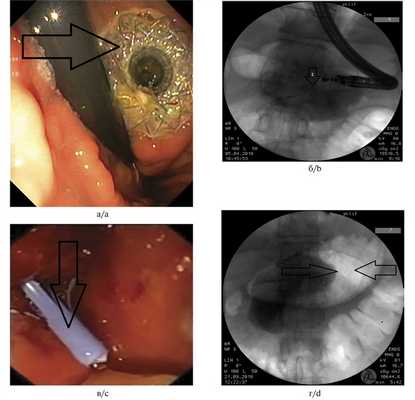

Пластиковые стенты применяли при наличии «зрелой» фиброзной капсулы толщиной от 3 до 9 мм и однородном содержимом кисты. Металлические саморасширяющиеся стенты устанавливали в отсутствие капсулы, при инфицированном содержимом и наличии секвестров (рис. 2). Рис. 2. Состояние после цистогастростомии. а — саморасширяющийся стент в просвете инфицированной кисты указан стрелкой (изображение получено при эндоскопической ультрасонографии); б — саморасширяющийся стент в просвете инфицированной кисты указан стрелкой 2 (по данным рентгенографии); в — пластиковый стент в просвете неинфицированной кисты указан стрелкой (изображение получено при эндоскопической ультрасонографии); г — пластиковый стент в просвете неинфицированной кисты указан стрелками (по данным рентгенографии). a — self-expanding stent inside infected cyst is indicated by the arrow 2 (us); b — self-expanding stent inside infected cyst is indicated by the arrow 2 (X-ray); c — plastic stent inside sterile cyst is indicated by the arrow (us); d — plastic stent inside sterile cyst is indicated by the arrows (X-ray).